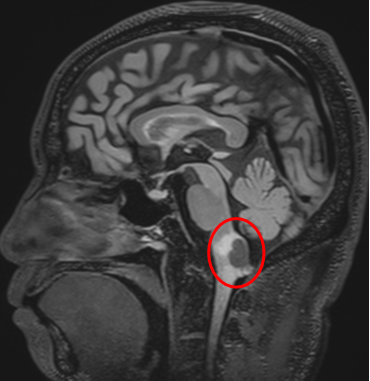

影像

和巴教授同為德國(guó)人的Z先生,長(zhǎng)期在中國(guó)生活。當(dāng)不幸查出“延髓背側(cè)占位”,雖然已經(jīng)咨詢(xún)過(guò)多個(gè)國(guó)家的神經(jīng)外科醫(yī)生,巴教授的回復(fù)讓Z先生對(duì)于手術(shù)充滿(mǎn)信心,最終選擇在亞洲神經(jīng)外科臨床、科研、教學(xué)基地——北京天壇醫(yī)院接受巴教授主刀的手術(shù)。